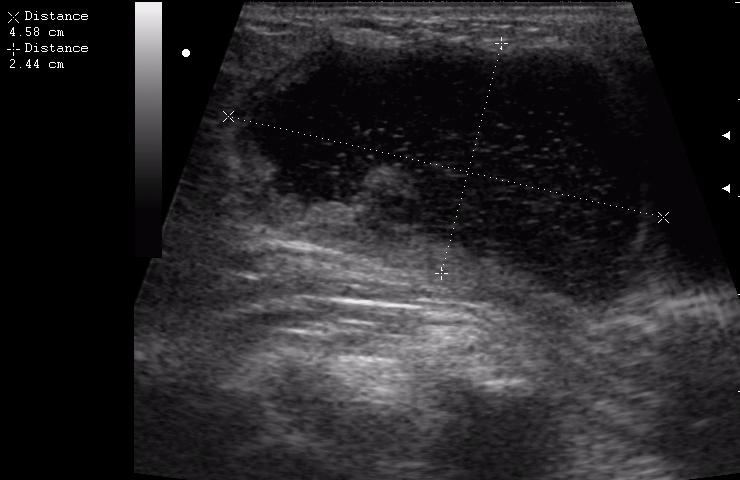

В клинику обратилась мать 11-летней девочки с жалобами на появление припухлости в подключичной области справа. Впервые заметили в феврале. За 4 месяца не интенсивный рост образования, с переходом на переднюю поверхность плеча, где кожа над ним на ограниченном участке (1.5-2см) имеет багрово-синюшную окраску.

(с д-зом Гематома(?) направлена на УЗИ)

достоверной связи с мышцами не увидела. Но на задней проекции включения определяется солидное образование. это может быть лимфоузел?